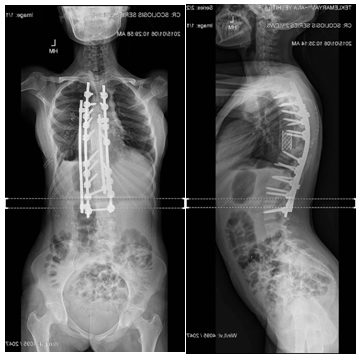

The patient had an uneventful recovery and remained neurologically intact. At the 2 year follow up the clinical improvement was satisfactory and the radiographs demonstrated a solid fusion and intact instrumentation. Her lumbar lordosis was 87 degrees and her global thoracic kyphosis was 77degrees (Figure 13 & 14).

Figure 13 Post-Op Full Spine Standing AP View.

Figure 14 Post-Op Full Spine Standing Lateral View.